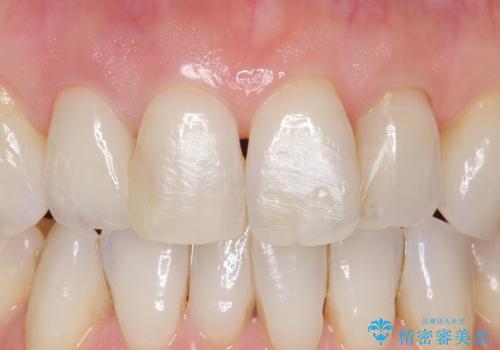

前歯が取れてしまった ジルコニアクラウンでの修復

他の歯との調和のとれたクラウンを装着することができ大変喜んでいただけました。